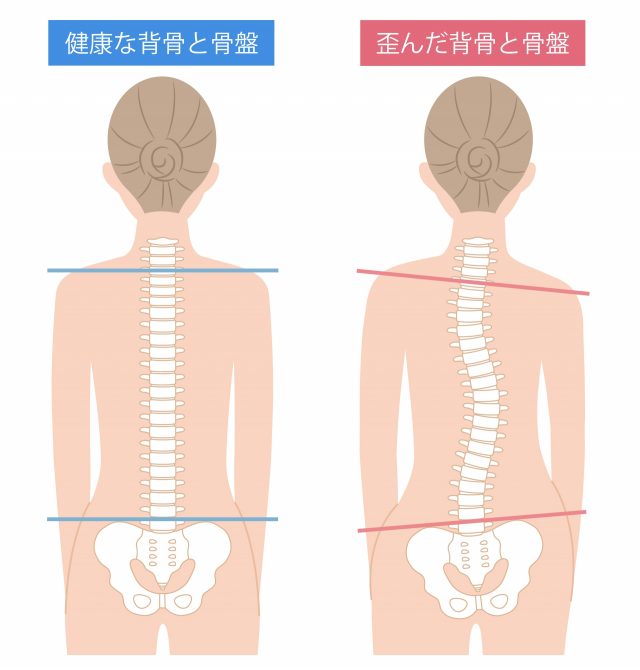

そして椎骨(背骨)が乗っている仙骨を両側から挟みこんでいる関節の為、関節が緩み圧力が低下すると仙骨の傾きが起こり、同時に背骨も傾き姿勢が悪くなり、徐々に側弯症や猫背といった背骨の疾患を引き起こします。

ですのでいくら背筋を伸ばそうとして意識しても、筋力で頑張っていても長続きせず、気が付くと背中が丸くなってしまいます。

仙腸関節の緩みを戻し関節の圧力が高まれば、仙骨の傾きが解消され、骨同士が安定するので自然と背筋が伸びるようになるのです。